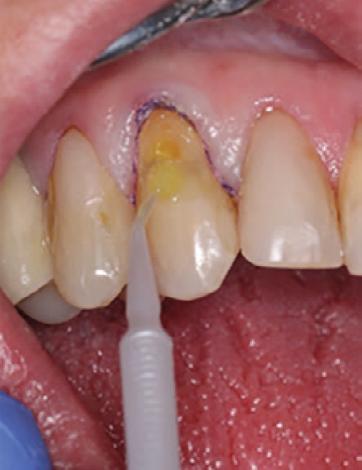

To improve isolation and soft tissue access, a retraction cord was placed before initiating the procedure (Fig. 2). The tooth was evaluated using a caries indicator dye (Kuraray Noritake Dental), helping to identify any remaining infected tissue beneath the dislodged composite (Fig. 3). Decay removal was completed with a diamond bur, and the enamel was bevelled using a starburst pattern to enhance aesthetic blending (Fig. 4). This preparation design was chosen for visual integration rather than bond strength enhancement.

Etching and Bonding

Selective etching of the enamel was performed using a phosphoric acid etchant, followed by rinsing and air drying (Fig. 5). CLEARFIL™ Universal Bond Quick 2 was then applied according to the manufacturer’s protocol: a three second application, gentle airdrying, and light-curing for 20 seconds (Fig. 6).